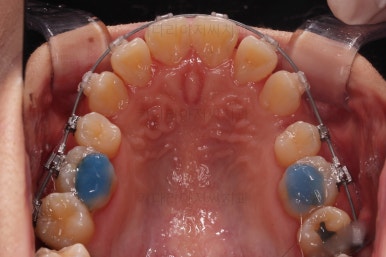

아랫니가 매우 밑으로 많이 내려온게 보이시죠?

과개교합은 비교적 초반에 개선이 되었습니다.

아래 앞니의 높이가 개선된 뒤, 아랫니도 가지런하게 해줍니다.

윗니도 어느새 치아를 뽑은 공간이 많이 줄었네요.

아랫니도 발치를 하고요.

윗니는 아랫니가 뒤로 들어가는 만큼 더 뒤로 밀어야 되기 때문에 미니스크류를 이용해서 뒤로 당기기를 해줍니다.